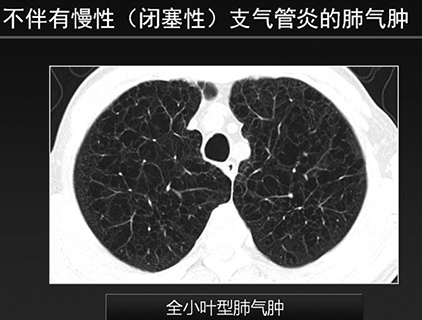

2.氣道病變優勢型︰全肺氣腫指數大於35%,氣道壁厚度大於或等於1.75mm。(如下圖所示)

長久以來,慢支肺氣腫幾乎成了一慢阻肺的代名詞,但有了胸部CT後,根據支氣管壁和管腔的改變,不同類型的肺氣腫已經清晰可辨(如附圖所示),從中也發現了兩者不一定密切相關。所以醫生們必須從影像學角度轉變這個陳舊觀念。同時也要應該清楚一點︰慢性支氣管炎和肺氣腫兩者可以並存,都會導致肺功能下降,但兩者並不存在因果關係。◇